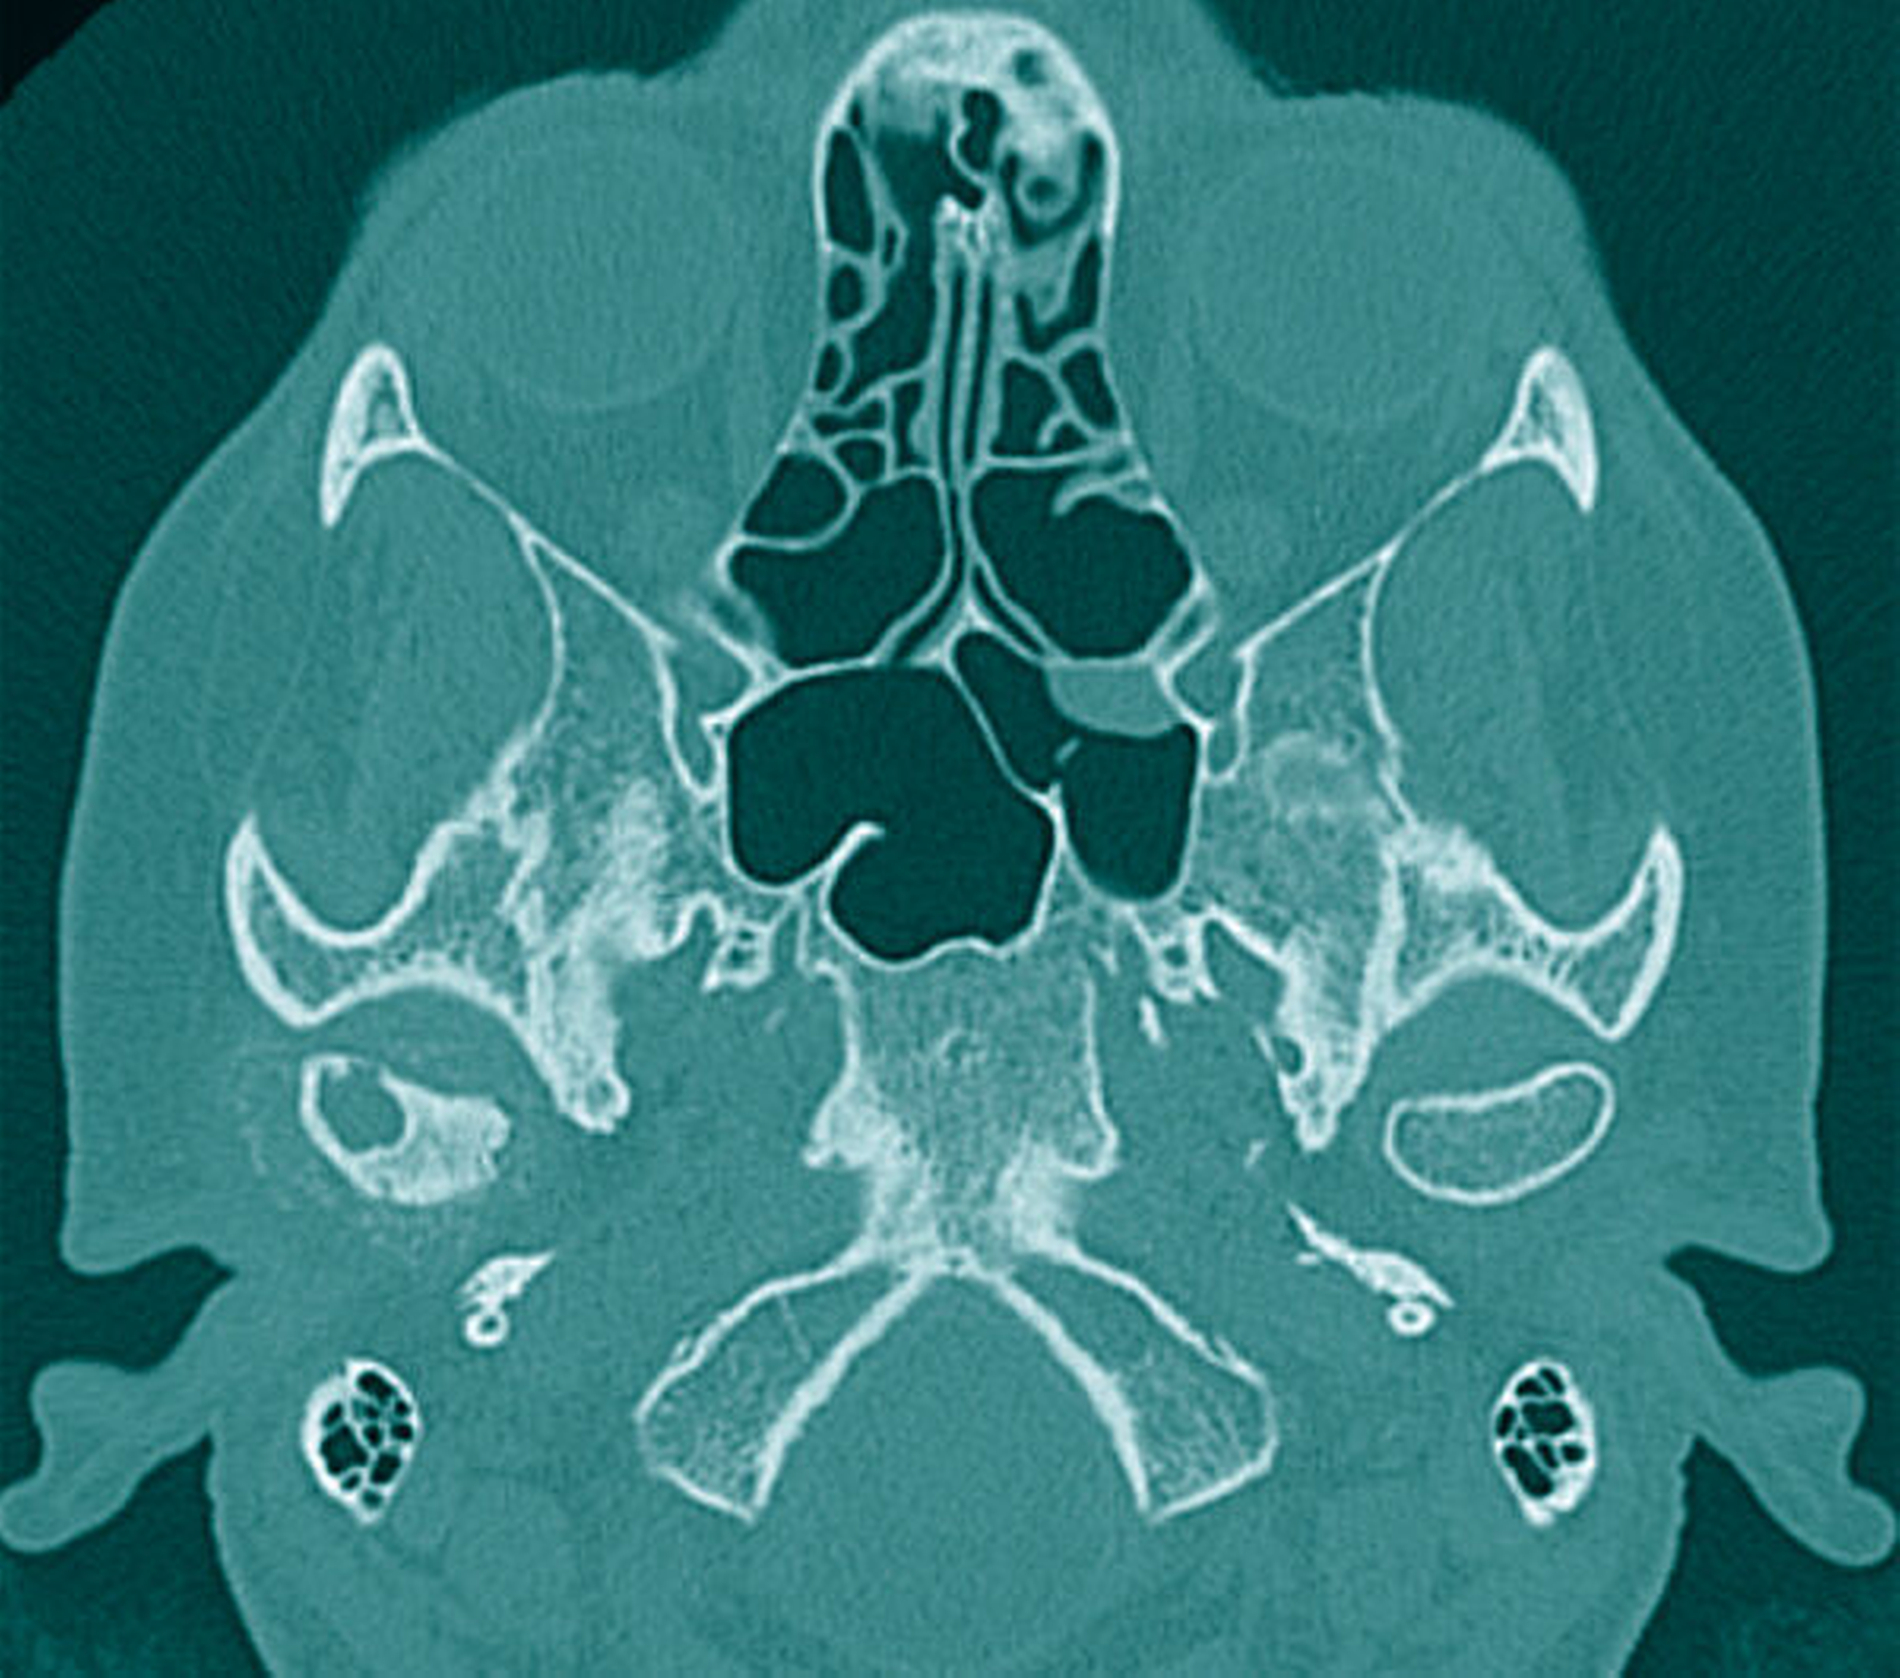

Zur genaueren Eingrenzung und Beurteilung der Knochenstrukturen wurde allerdings eine zusätzliche CT-Untersuchung empfohlen, die im Hinblick auf eine navigationsgestützte Probenentnahme nach kranialem Einbringen von vier Markierungsschrauben durchgeführt wurde. Hierbei wiederum ergab sich in Korrelation mit der bereits durchgeführten MRT-Untersuchung eine Mehrsklerosierung des Capitulums rechts mit geringen Arrosionen im apikalen Anteil und einer glatt begrenzten Zyste. Somit wurde von den radiologischen Kollegen die Verdachtsdiagnose eines Chondrosarkoms aufgestellt (Abbildung 2).

Während sich intra- und periartikuläre Verkalkungen gut mittels CT darstellen lassen, erfordert die Beurteilung der angrenzenden, oft neoplastisch anmutenden, aufgetriebenen, weichgewebigen und knorpeligen Strukturen eine ergänzende MRT-Untersuchung [Aoyama et al., 2000; Koitschev et al., 2003]. Mögliche, nur schwer abzugrenzende neoplastische Differenzialdiagnosen sind dabei das Osteochondrom, das Chondrosarkom oder das Chondroblastom [Loro und Bjørnland, 2020]. Wie im Fallbeispiel ist das – wenn auch seltene – Vorkommen kapitulär lokalisierter synovialer Zysten beschrieben [Maribo et al., 2019]. Synovialzysten sind echte synovial-ausgekleidete Zysten, die aus einer verlagerten oder exponierten Synovialschleimhaut entstehen und mit dem Gelenkkavum kommunizieren. Als Ursache vermutet man dabei eine primär traumatische oder postentzündliche Genese mit der Entstehung eines erhöhten intraartikulären Drucks [Vera-Sirera et al., 2013].